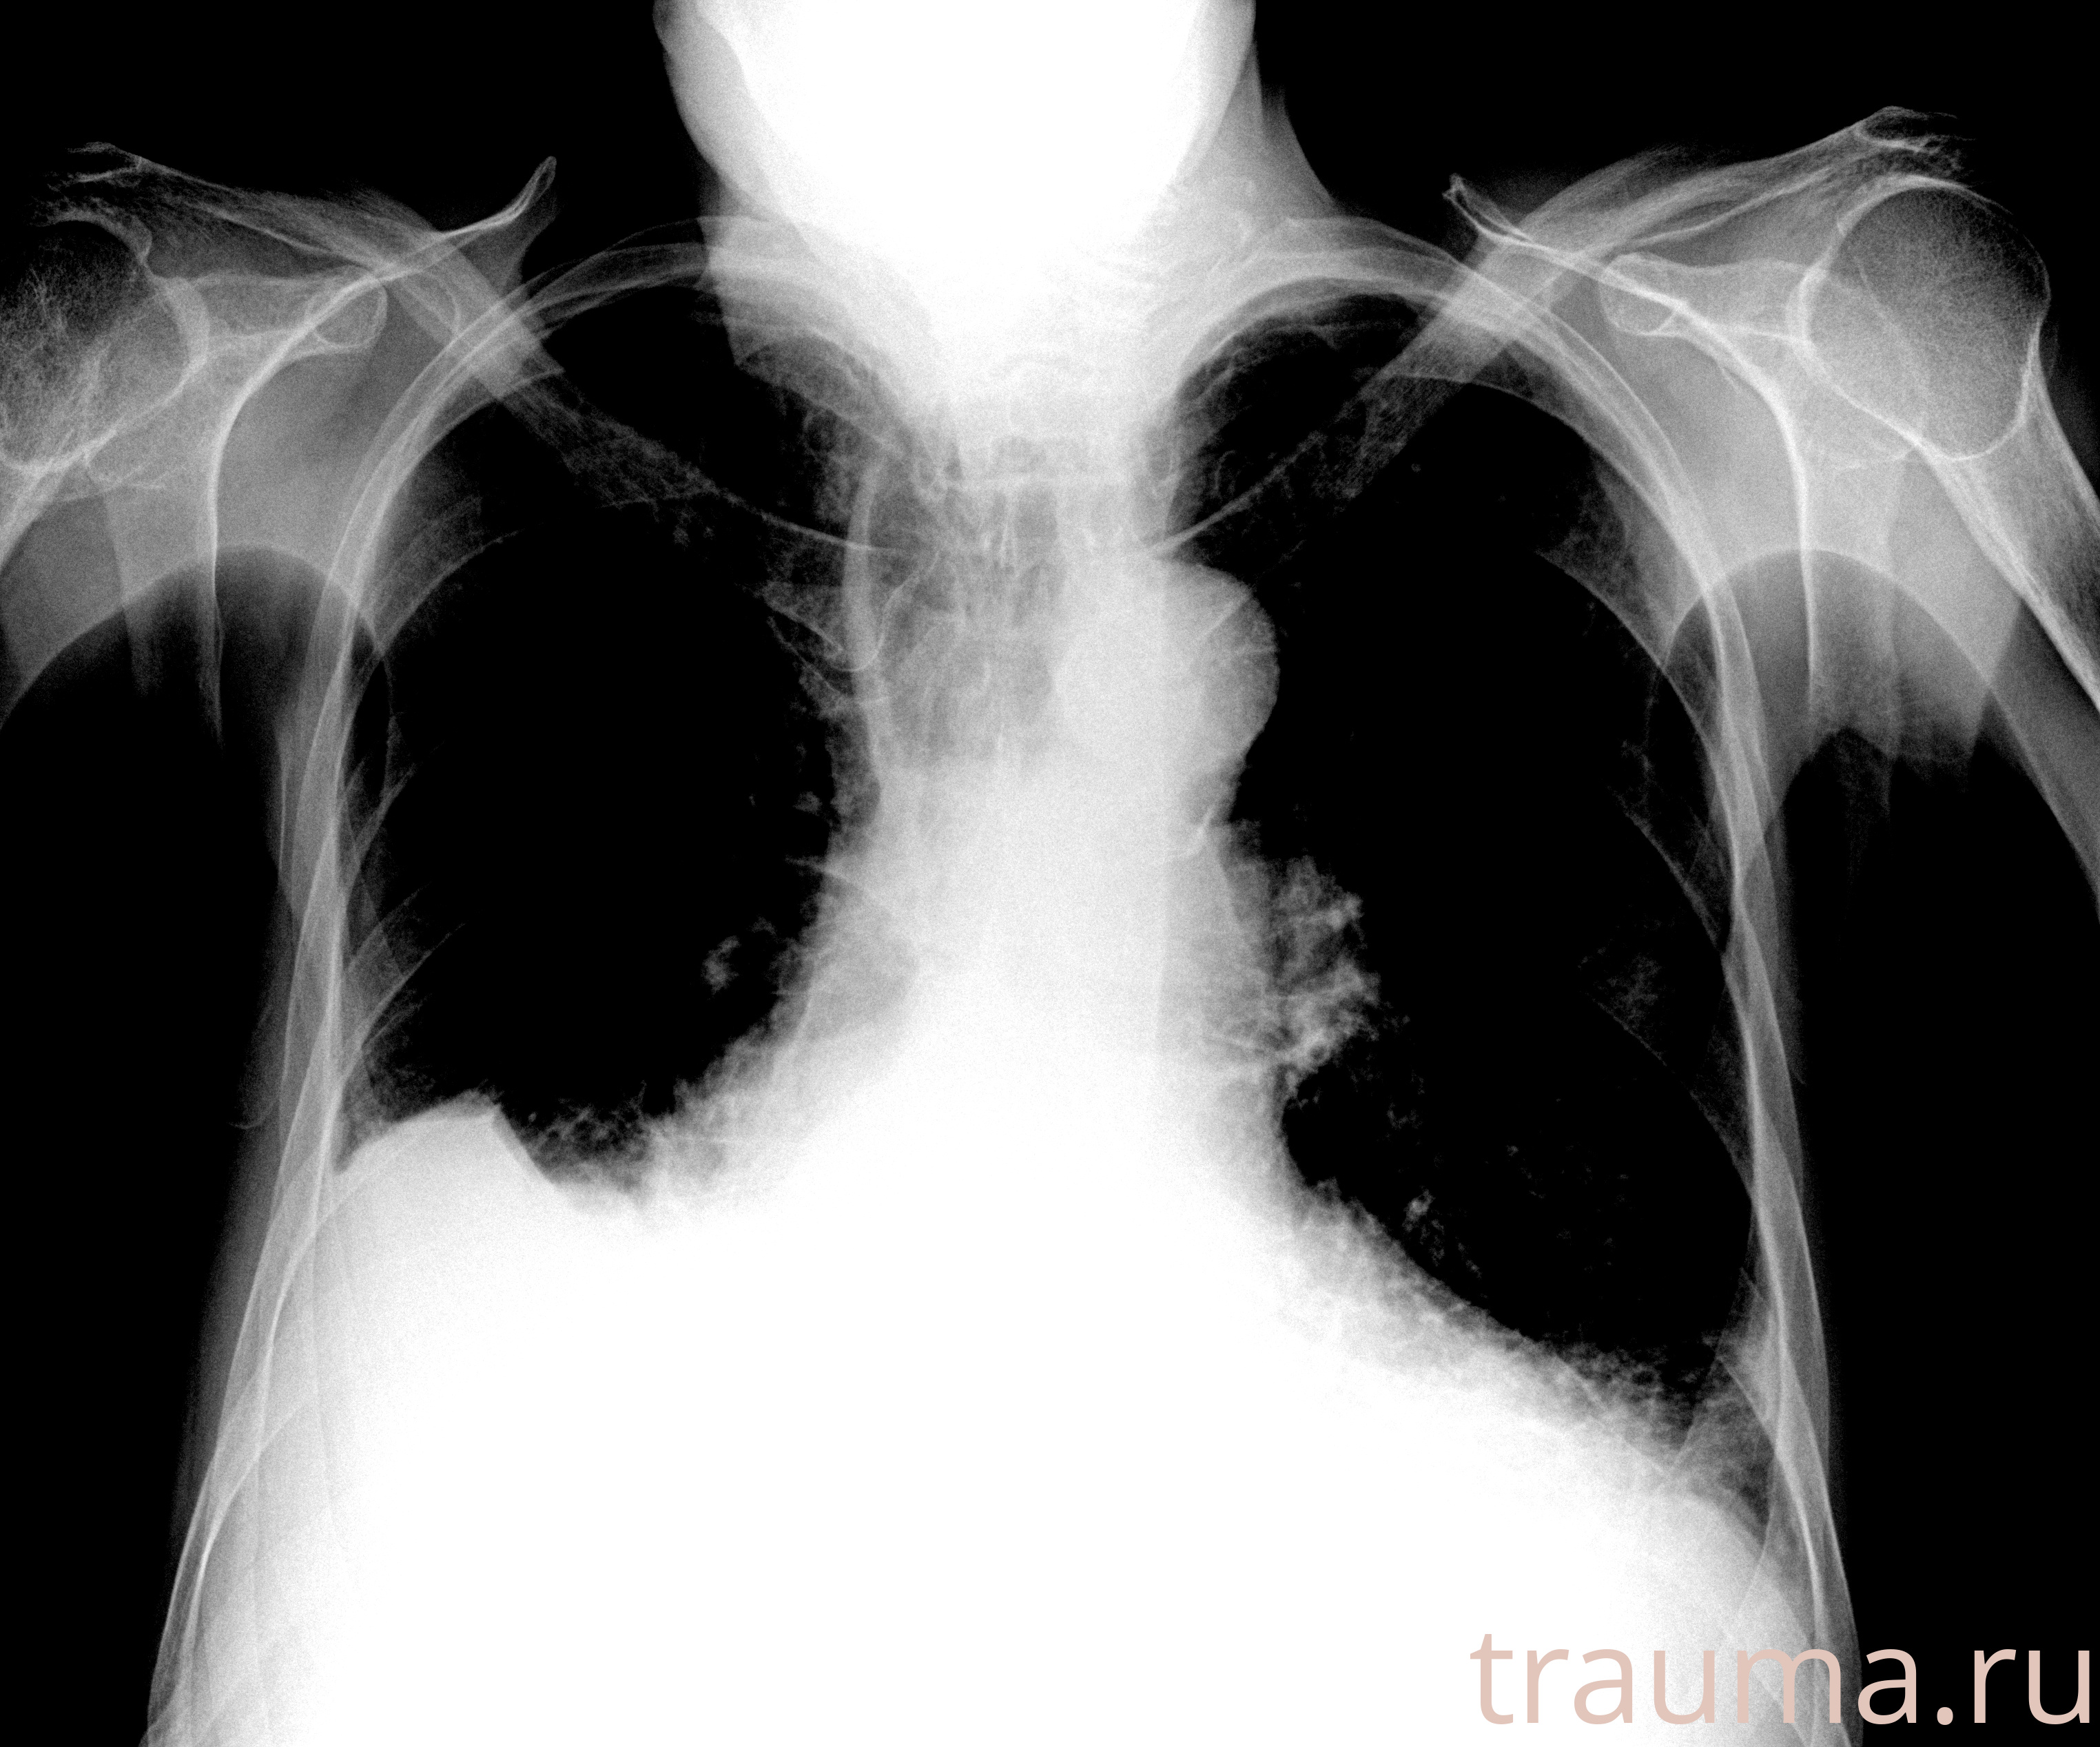

Рентгенограммы

Рентген на дому: по вашему адресу приезжает врач-рентгенолог, травматолог-ортопед с мобильным рентгеновским аппаратом, проводит диагностику травмы или заболевания, делает необходимые рентгенограммы, дает рекомендации по дальнейшему лечению. Получить качественные снимки в домашних условиях возможно благодаря уникальной методике, разработанной МосРентген Центром для института  Склифосовского

Яркость: 1   Контраст: 1   Инвертировать: 0 Увеличение: 1

Перетаскивайте мышь вверх/вниз для контраста, влево/право для яркости. Прокрутка колесом изменяет масштаб. Нажмите Сбросить для возврата к исходному изображению. При увеличении держите мышь в той области, которую хотите рассмотреть.